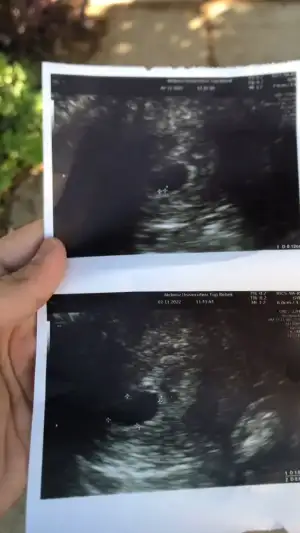

hayırlısı artık canım. cumartesi belli olcak ikizmi tek miAyyy senınde ıkız gıbı canım hadı hayırlısı olsun ınsallah

Oyy maşallah canım sağlıklı büyüsünBen de bugün 6+3te kalp atisini duydum :) iki kese olusmus birinde duyuldu digerindeki yolk kese kadar büyük oldugundan ona ümitsiz konustu

Evet alttan eger ikinci kese olusursa ne mutlu bize :)

Maşallah Allahım esirgesin sağlıkla kucağına alırsın inşallah hafta ya onuda duyarsınSağolasın canım, gıttım doktora enox ıcın 10 kutu aldım rapor cıkardı. Keseye baktı 2 tanesınde kalp atışı var dedı ama bırınde duyamadım dedı. Görüntü de 3 keseyi de gördü. Bir hafta 10 gün sonra tekrar gel dedi. Dün akşam üzeri silnmeyle gelen az bişey kahverengi akıntım oldu. Gelişmeler böyle kızlar sizde nasıl gidiyor

Hayırlı olsun inşallah diğerini de duyarsın benim kinin biri 1 2 gün geriden geliyor belki seninki de öyledirBen de bugün 6+3te kalp atisini duydum :) iki kese olusmus birinde duyuldu digerindeki yolk kese kadar büyük oldugundan ona ümitsiz konustu